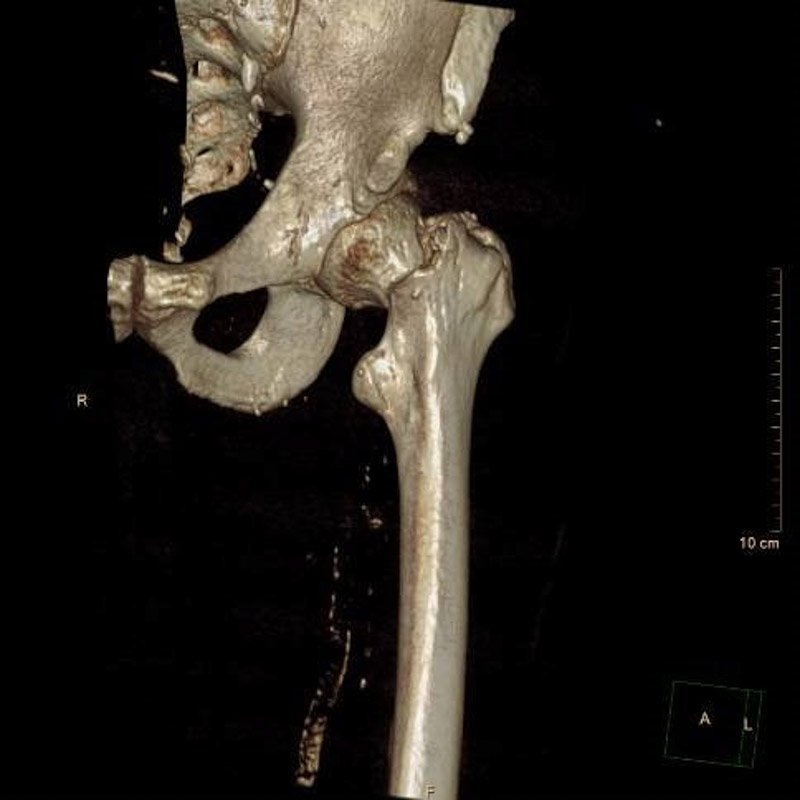

髖部即我們平常所說的“胯骨”部位,是連接人體軀干和下肢的重要樞紐,也是人體最大、最重的關節。髖部骨折主要指髖臼骨折和股骨近端骨折,其中股骨頸骨折和股骨轉子間骨折是臨床上最常見的骨折類型,約占老年髖部骨折的90%以上。

經過周密的術前準備,6月30日,在麻醉科團隊成功實施腰椎管內麻醉后,創傷骨科團隊為患者進行左側人工股骨頭置換術,手術過程順利。術后羅老伯恢復良好,圍術期內無心肌缺血癥狀發作,監測心電圖無動態改變。